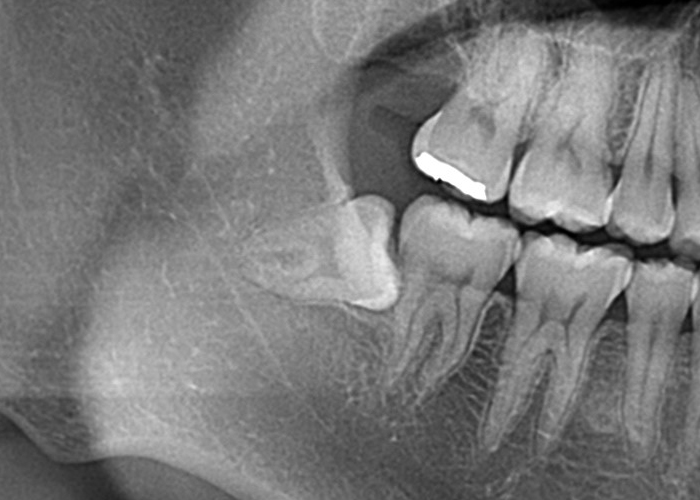

半埋伏智歯(部分的に露出している)

半埋伏とは、親知らずの一部が歯肉の下に埋まっており、一部が口腔内に露出している状態を指します。

露出している部分には、歯垢や食物がたまりやすくなり、炎症や感染、虫歯のリスクが高まる場合があります。

また、半埋伏の親知らずは、周囲の歯や歯肉に圧迫を与え、痛みや不快感を引き起こすこともあります。

さらに、半埋伏の親知らずが隣接する歯に対して圧力をかけることで、歯列の乱れや移動が起こる場合もあります。